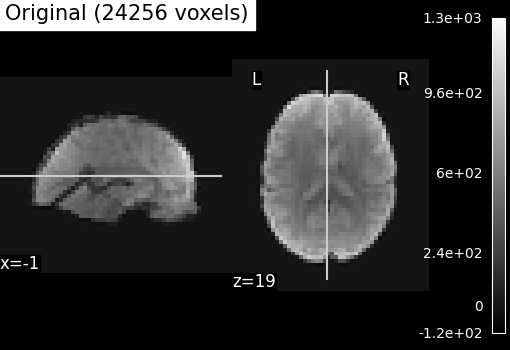

Compressed representation of ReNA clustering¶

We illustrate the effect that the clustering has on the signal. We show the original data, and the approximation provided by the clustering by averaging the signal on each parcel.

We can then compare the results with the compressed representation obtained with Ward.

plotting.plot_epi(

title=f"Original ({int(original_voxels)} voxels)",

Even if the compressed signal is relatively close to the original signal, we can notice that Ward Clustering gives a slightly more accurate compressed representation. However, as said in the previous section, the computation time is reduced which could still make ReNA more relevant than Ward in some cases.